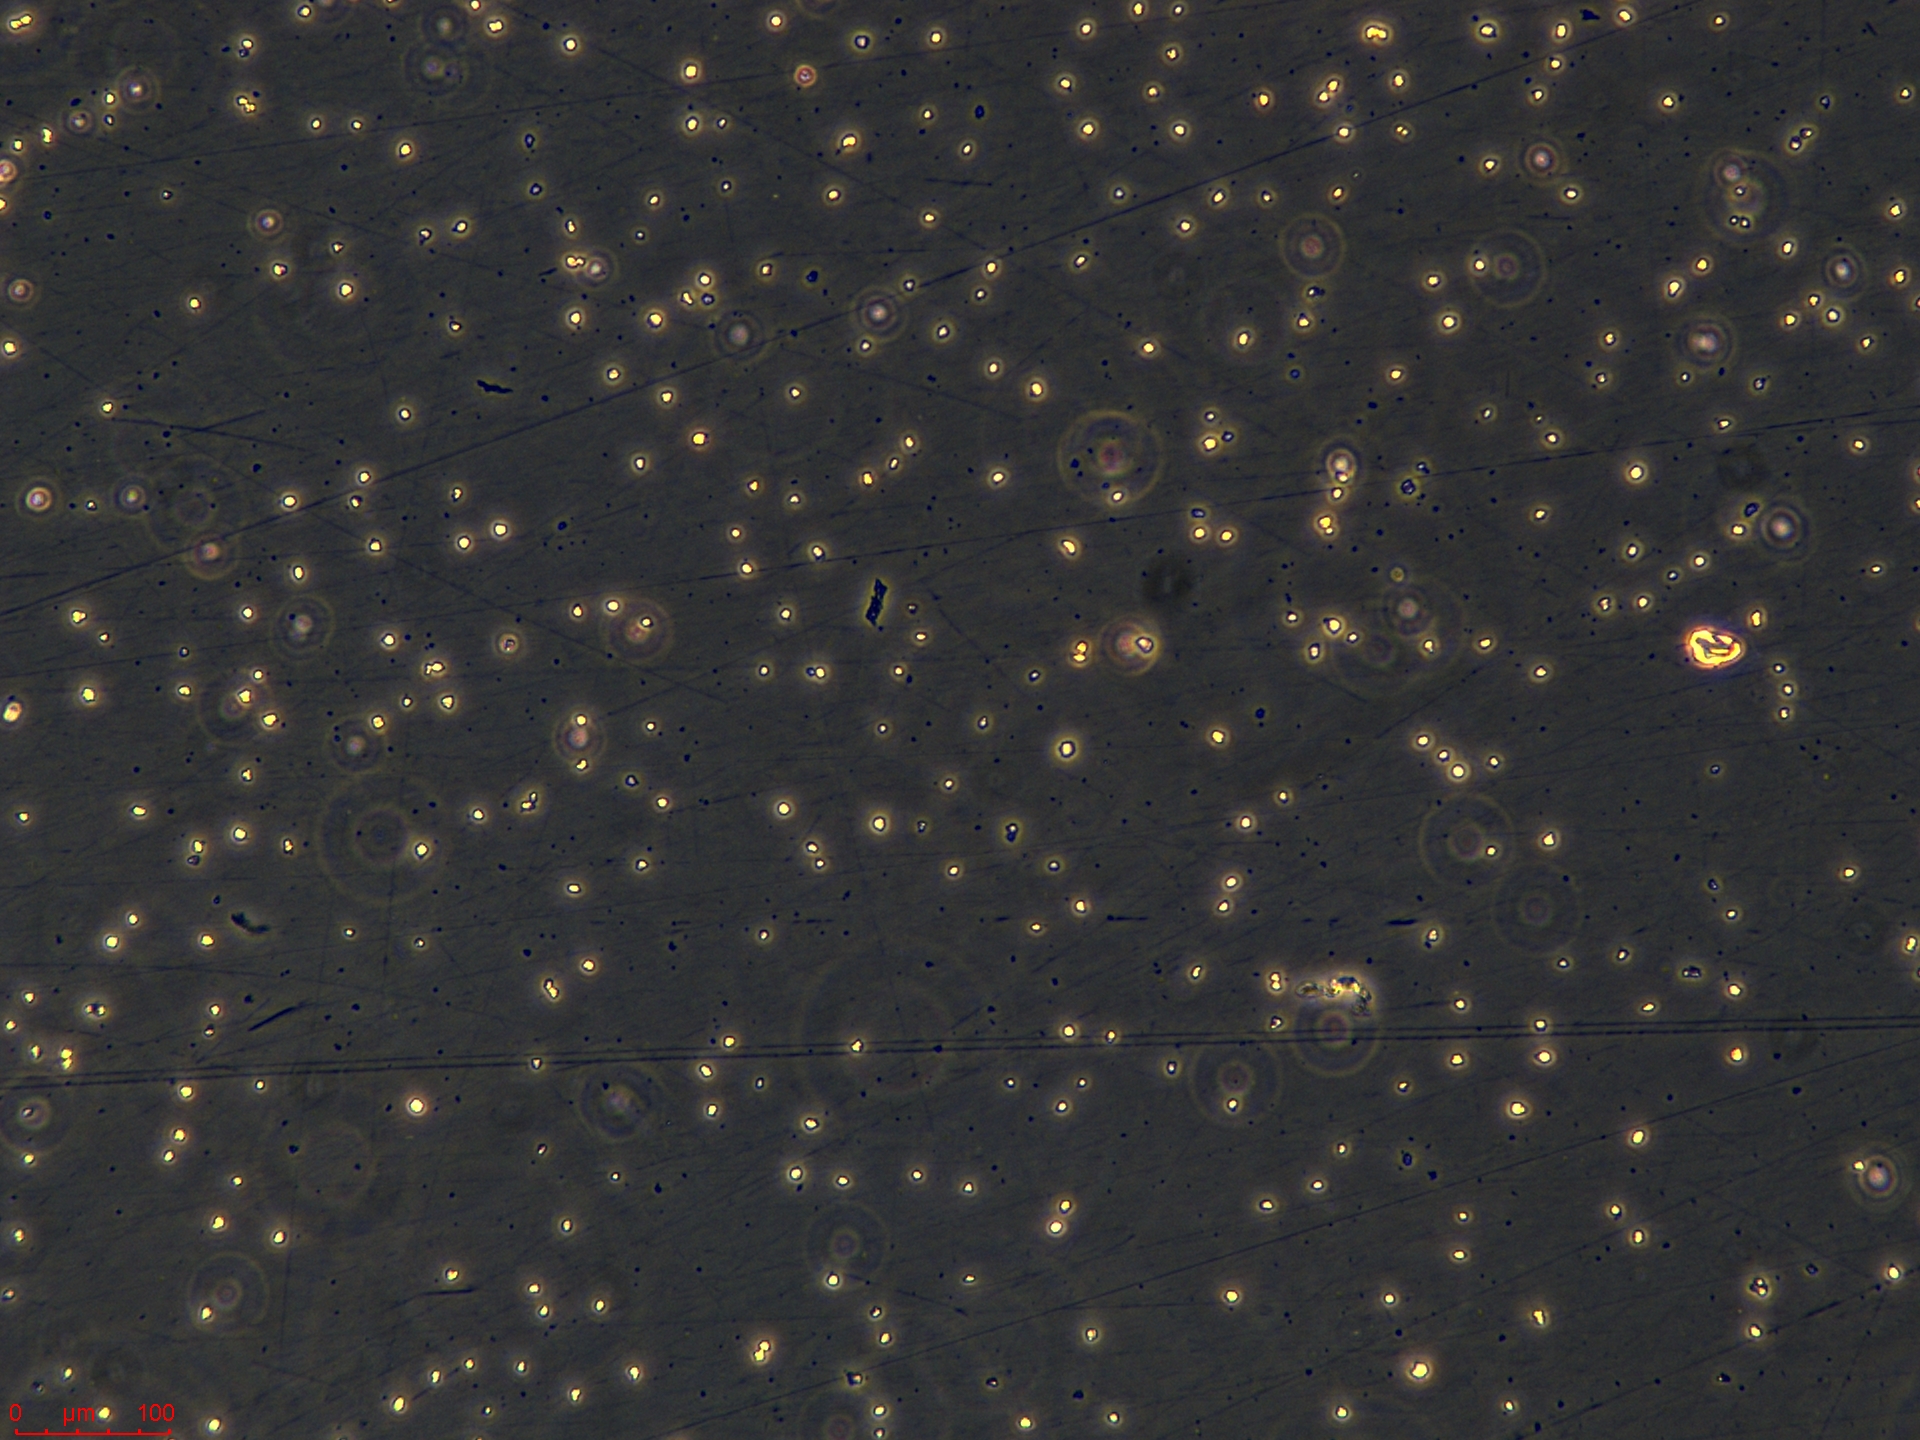

悬浮生长(Suspension)

分析核型,而且能分选出不同类型的染色体,做成人类每条染色体的 DNA 文库,可用于人类基因组研究、遗传病和癌症的诊断的研究。 免疫学研究 结合免疫荧光方法,流式细胞术可辨认和计数带有不同表面特异性抗原的细胞,例如用荧光素标记的免疫球蛋白鉴别T和B淋巴细胞,根据细胞表面抗原的不同,进一步分辨出不同的 T 和 B 淋巴细胞亚群,以及测定每个细胞所带抗原的数量、密度及其动力学参数等。也可用流式细胞分选技术将带有「+」和不带有「-」的某种特异抗原的细胞群体分类收集,供研究其功能特性。 流式细胞